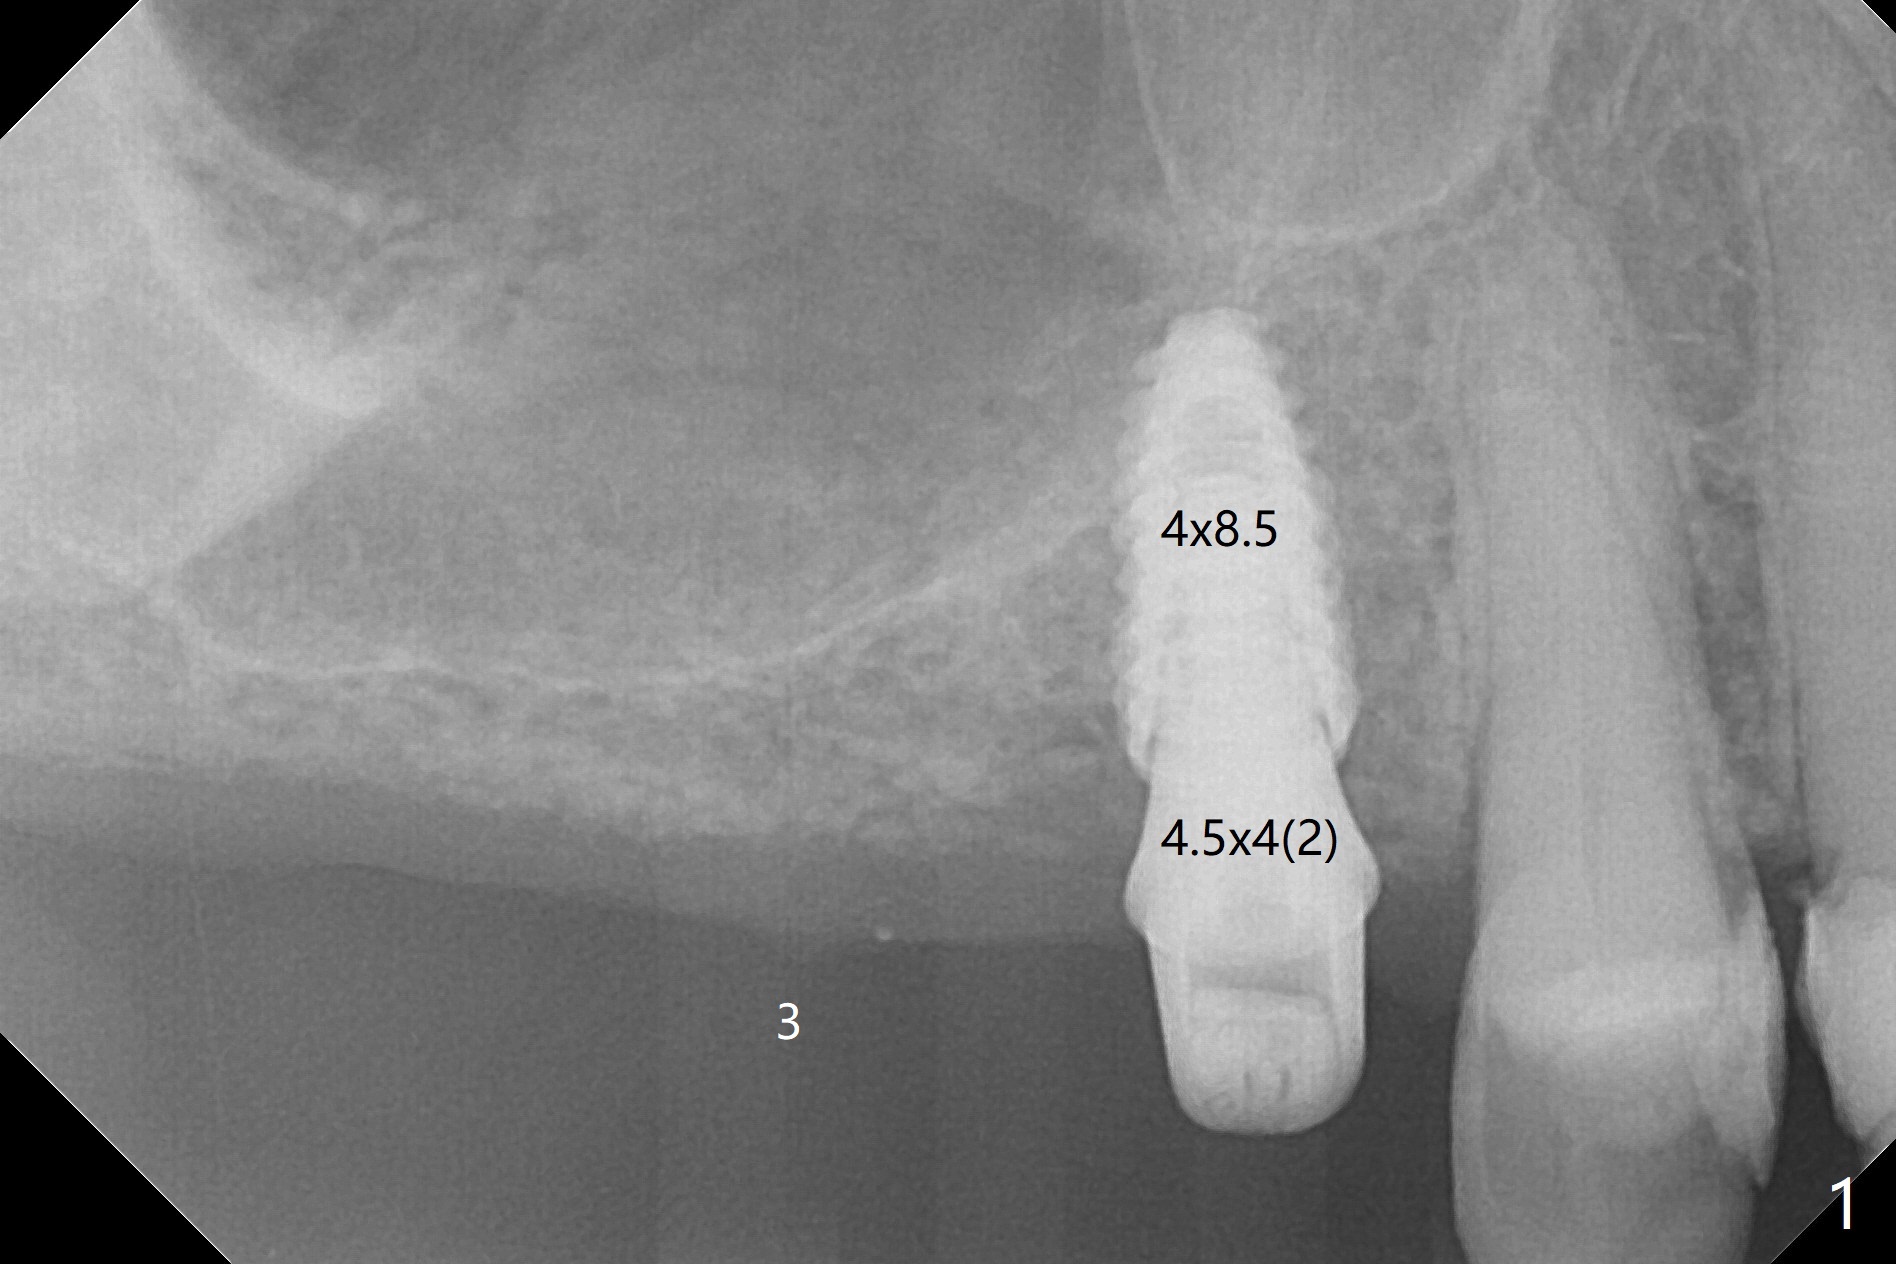

Osteotomy at #3 is performed last (Fig.1,2); as planned, a 4 mm cortical tap is used with guide for sinus lift. Unfortunately the sinus membrane is perforated. Implant placement is aborted. Instead Osteogen plug is inserted into the osteotomy, which is fixed in place by acrylic extending from the provisional at #4. Osteotomy for #3 implant will be attempted with control of the depth in 4 months. The patient has allergy to Amoxicillin (rash). When switching to Clindamycin, she develops diarrhea and loses 10 pounds. There is no abnormality at the site of #3 or 4 nearly 3 months postop (Fig.3). The next surgery will be most likely conducted without antibiotic 4 months postop. Try to draw blood for PRF. Take PA for #12 and 13 for possible impression. Remove the 3 temporary crowns, seat the guide across the arch and use no-stop fixture mounts at #4, and possibly 12 and 13. Follow the original drill sequence (check perforation after each drill, Fig.11) and use DIONavi sinus approach kit. Also load an appropriate stop for the round bur for sinus lift before hand. Mixture allograft with Metronidazole and PRF. In fact everything goes on as smoothly as planned. Osteotomy at #3 is underprep (3.5 mm in diameter drill instead of 4.0). The sinus floor appears to remain to be absent; 3.2 mm round bur is used for lift, alternating with water pumping. Following insertion of 3 pieces of PRF membranes and Vanilla Graft (Fig.4 *), a 4x10 mm dummy implant is placed. After additional bone graft (Fig.5 *), a final 4.5x7.3 mm implant is placed ~10 Ncm. The implant is placed deeper ~ 1 mm, followed by a 5.5x3 mm healing abutment (Fig.6). The implants at #12 and 13 seem to have osteointegrated (Fig.7). Impression is taken for #4, 12 and 13 with limited vertical space (Fig.8,9). An implant at #14 is being considered. There is faint bone graft around the apex of the implant 4 months postop (Fig.10). The implant sustains 25-30 Ncm torque when a 5.2x4(3) mm cemented abutment is placed. A permanent crown is cemented nearly 5 months postop (Fig.11). For the best cosmetic and masticating results, the occlusal surface should have certain degree of morphology, such as the buccal cusps (Fig.12 white curved lines). The abutment at #3 is placed and torqued to 30 Ncm before re-cementation of the repaired crown (increased occlusal surface contact). In fact the abutment at #4 is incompletely seated with a gap (Fig.13 <). The composite at #5 is dislodged while #3 crown is being repaired (*). The abutment at #4 is loose >1 year post cementation. The abutment remains incompletely seated (gap and longer apical space (double arrows)) when the abutment/crown complex rotates lingual mesiobuccal (Fig.14 curved arrow). Further proximal reduction and lingual rotation distobuccal leads to complete seating (Fig.15). It appears that incomplete seating at #13 is associated with hex mismatch (Fig.16, large apical space), which will be fixed next visit. One week later, the crown and abutment of #4 are seated together after crown repair (Fig.17). Since the abutment margin is subgingival, the crown is cemented, removed with abutment for residual cement removal and reseated with the abutment with torque at 30 Ncm. After this, the crown and abutment of #13 is reseated after mesiobuccal surface is trimmed (Fig.18), followed by pick up impression. A few days later, the crown/abutment are inserted together smoothly, the former cemented and the complex unscrewed for residual cement removal and last torqued at 30 Ncm without any X-ray confirmation.